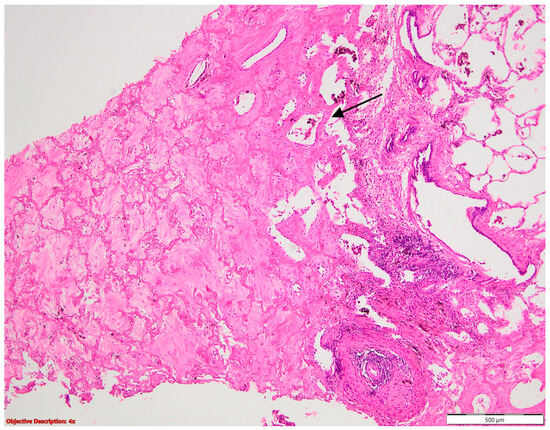

Aspiration pneumonia (Figure 13) is often associated with glottal incompetence and ciliary dysfunction, which can result from radiation therapy [32]. The tumor invasion of the vagus or recurrent laryngeal nerve is a known complication in individuals with lung cancer [32]. All these may cause one to be predisposed to aspiration pneumonia in lung cancer. In our study, we identified only one case of lung cancer, which underscores the relatively rare occurrence of this complication in our cohort. Nonetheless, the presence of lung cancer, particularly in conjunction with predisposing factors such as glottal incompetence and nerve invasion, heightens the risk of aspiration pneumonia. This highlights the importance of vigilance in identifying and managing such complications in patients with lung cancer, particularly those undergoing radiation therapy or presenting with neurological symptoms suggestive of nerve involvement.

Figure 13. Aspiration pneumonia. Multiple histiocytes with intracytoplasmic cholesterol () are present in the peribronchiolar area (→); HE, 40×.